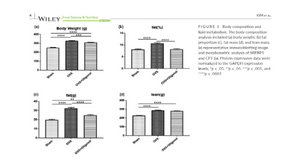

The iNSiGHT system can be used to assess changes in body composition following the delivery of a target compound at an effective dose. This can be accomplished by monitoring changes in bone mineral density and content over time, as well as assessing changes in fat and lean mass. In this case, researchers were looking at how polyphenol therapy affected a rat model of ovariectomy.

Image Credit: Kim, J. H., Lee, H., Kim, J. M., Lee, B.-J., Kim, I.-J., Pak, K., Jeon, Y. K., & Kim, K. (2022). Effect of oligonol, a lychee-derived polyphenol, on skeletal muscle in ovariectomized rats by regulating body composition, protein turnover, and mitochondrial quality signaling. Food Science & Nutrition, 10, 1184– 1194.

In this case, low-dose lithium supplementation was investigated and found to induce adipose tissue browning and sarco(endo)plasmic reticulum Ca2+ ATPase uncoupling in muscle.

Image Credit: Geromella MS, Ryan CR, Braun JL, Finch MS, Maddalena LA, Bagshaw O, Hockey BL, Moradi F, Fenech RK, Ryoo J, Marko DM, Dhaliwal R, Sweezey-Munroe J, Hamstra SI, Gardner G, Silvera S, Vandenboom R, Roy BD, Stuart JA, MacPherson REK, Fajardo VA. Low-dose lithium supplementation promotes adipose tissue browning and sarco(endo)plasmic reticulum Ca2+ ATPase uncoupling in muscle. J Biol Chem. 2022 Nov;298(11):102568. doi: 10.1016/j.jbc.2022.102568. Epub 2022 Oct 7. PMID: 36209826; PMCID: PMC9664358.